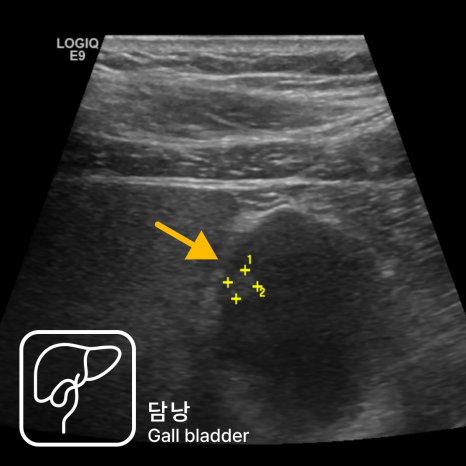

복부초음파에서 과거 5mm였던 담낭 용종이 약 1.6cm 크기의 단일 결절 형태로 커져 있는 것이 확인되었습니다.

병변은 내부 에코가 비균질하고 경계가 불분명하며, 담낭벽과의 접촉면이 일부 불규칙하게 보여 악성 가능성을 배제하기 어려웠습니다.